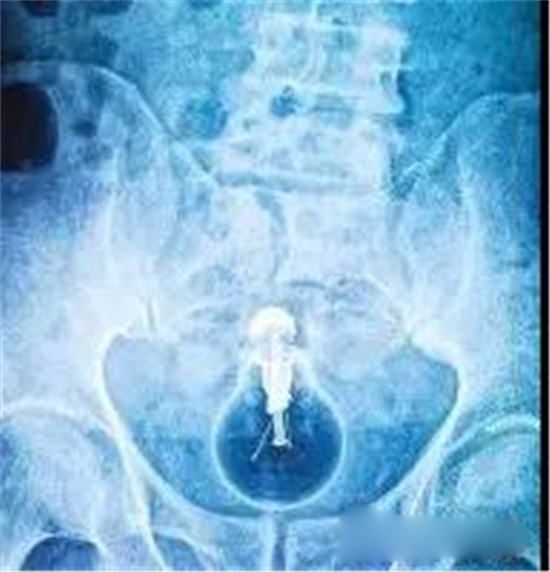

这是一个啤酒瓶。男性。

上面是一个啤酒瓶在大肠里。病人是男性。这是常见的肛门内异物。

这种情况,往往只要给病人打上全身麻醉,肛门松弛后,就可以用卵圆钳经过肛门把啤酒瓶拉出来。